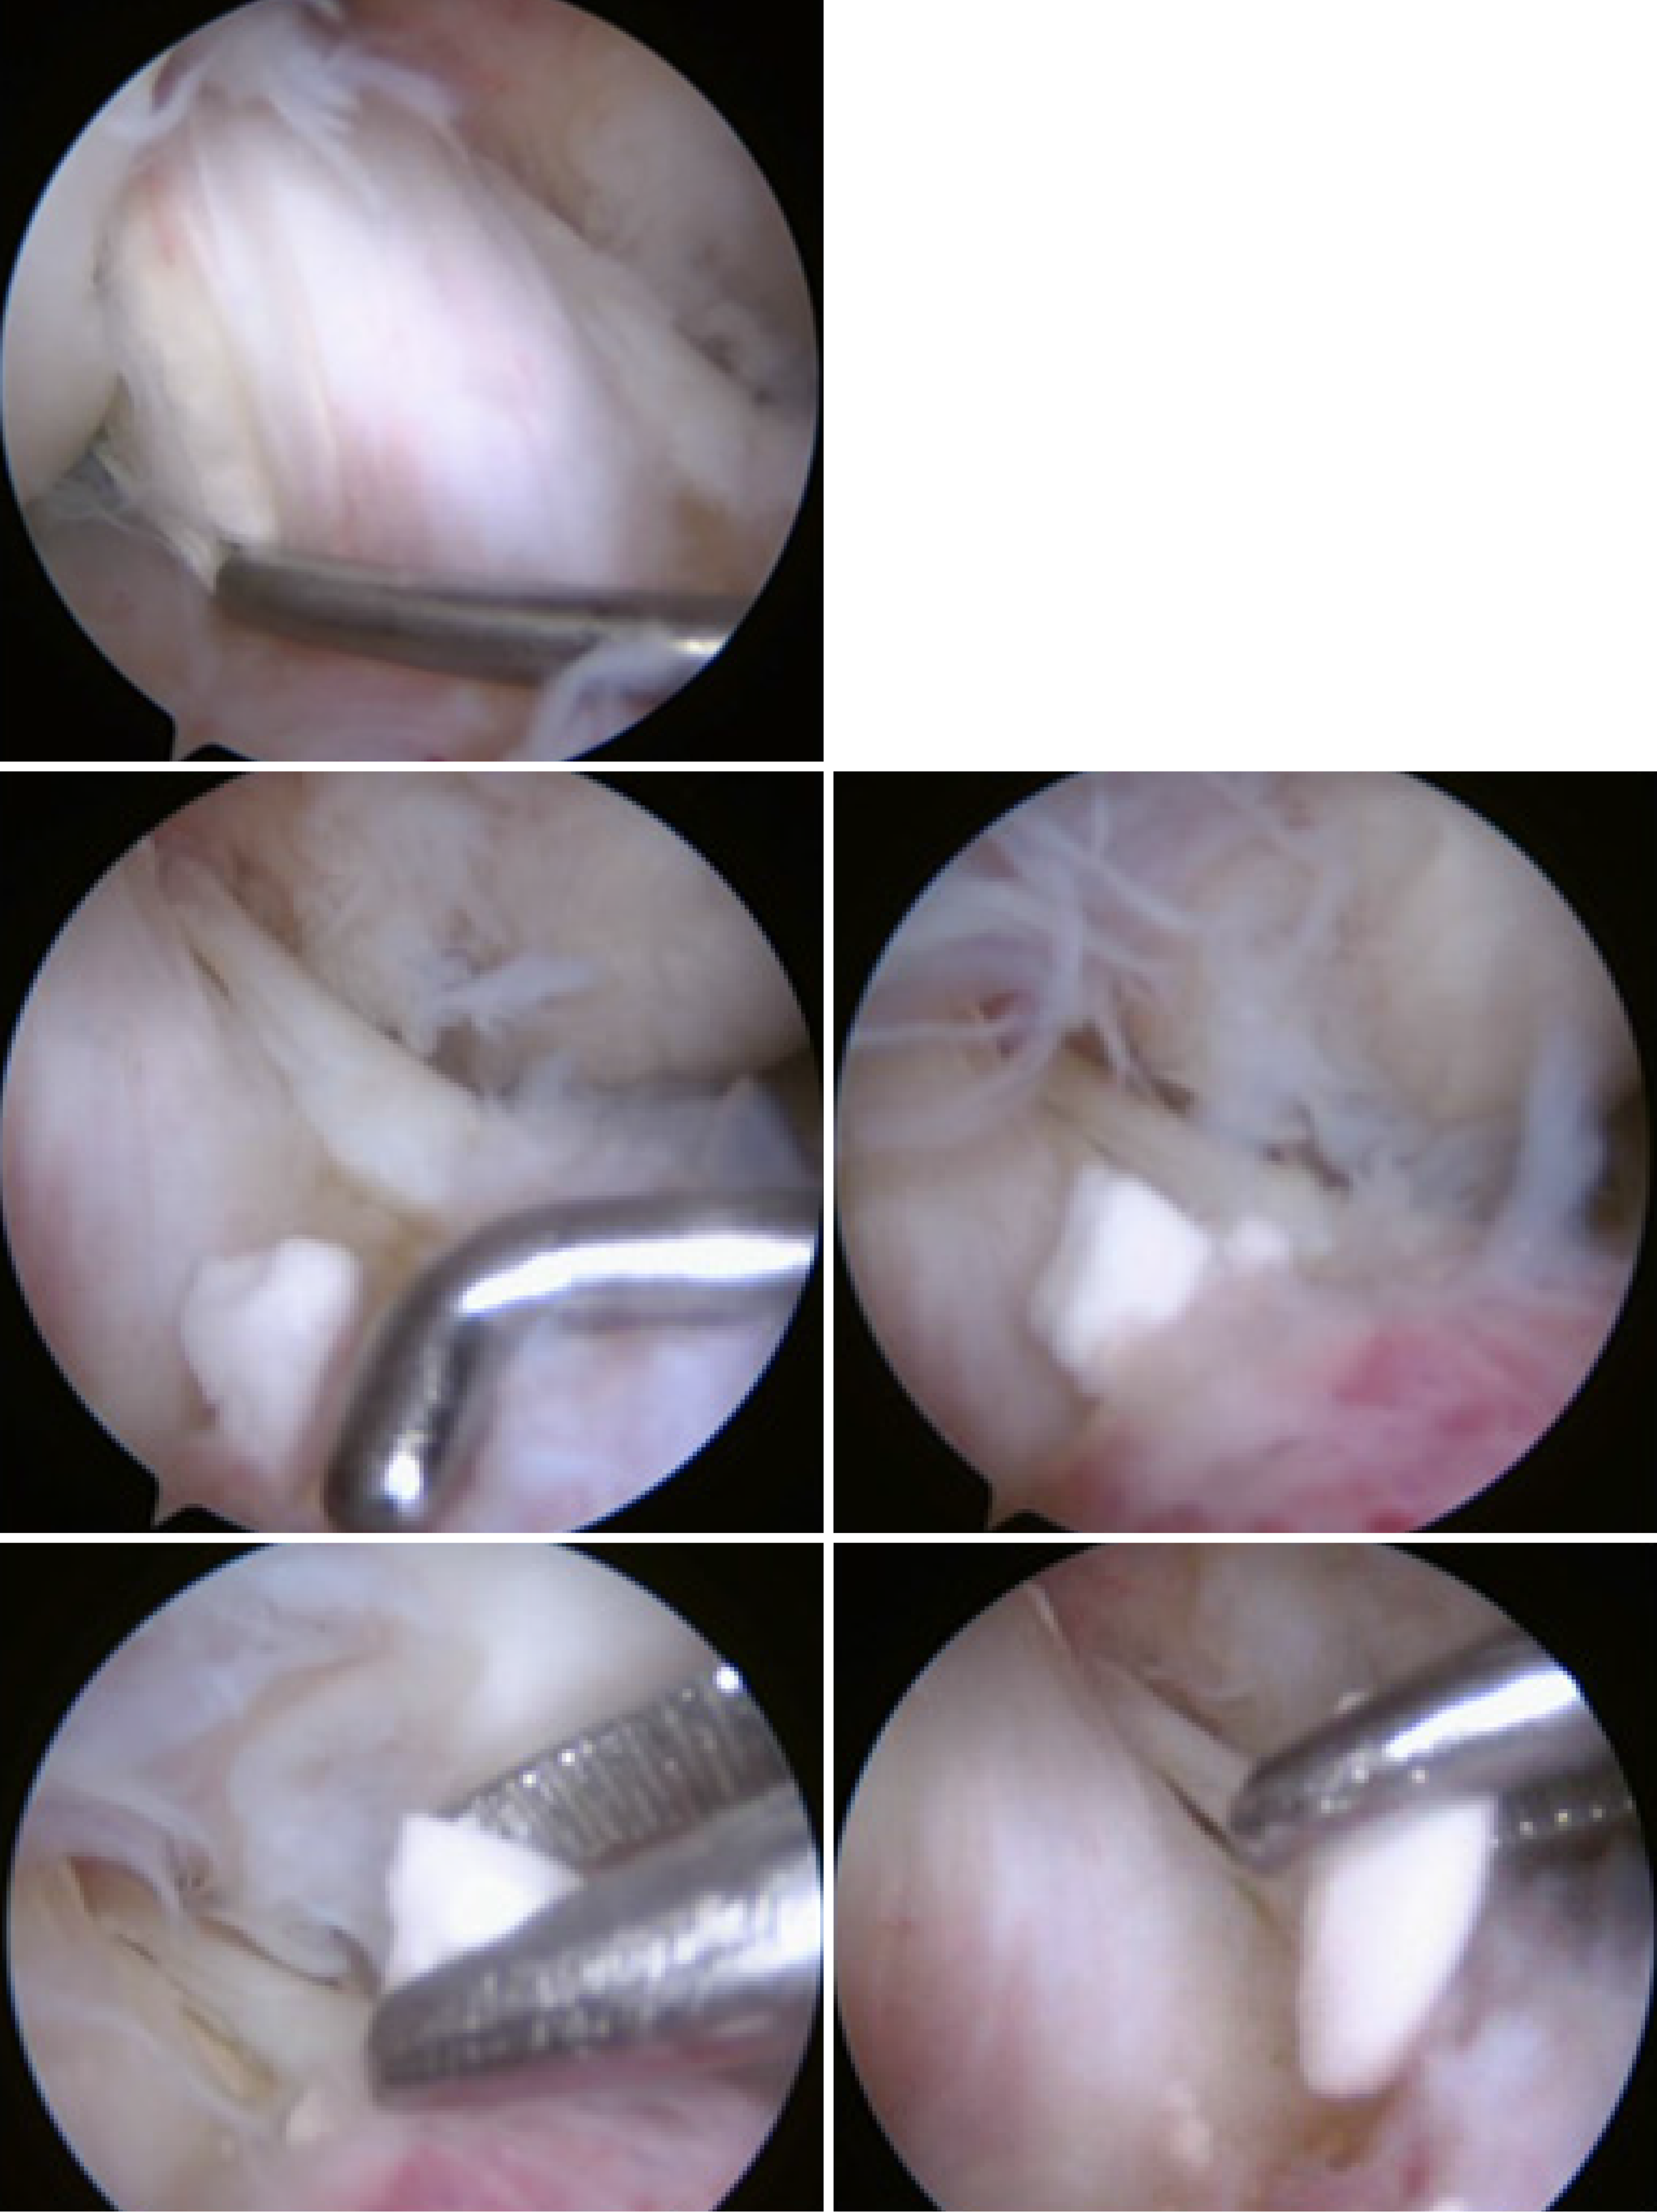

Figure 3

Arthroscopic image showing intact anterior cruciate ligament graft, and multiple broken intra-articular bioabsorbable tibial screws.